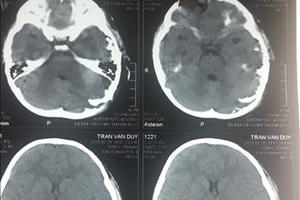

Bệnh viện Nhi Thanh Hóa cho biết, đơn vị vừa điều trị thành công cho bệnh 4 tuổi bị thương do chó cắn khiến sọ não hở ở vùng chẩm và thái dương trái.